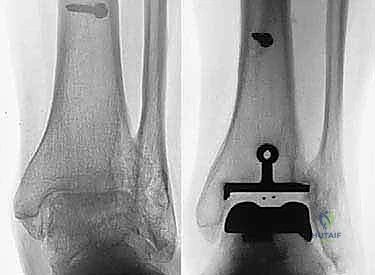

- الأشعة السينية (X-rays) بوضعية الوقوف: وهي الأداة الذهبية للتشخيص. صور الأشعة والوزن محمل على القدم (Weight-bearing X-rays) تظهر بدقة مدى تآكل الغضروف (ضيق المسافة المفصلية)، وجود نتوءات عظمية (Osteophytes)، وأي انحراف في المحور الميكانيكي للساق.

مفصل سالتو الأصلي هو ثمرة أبحاث أوروبية مكثفة. تم تطويره بين عامي 1994 و 1996، وبدأ استخدامه السريري بنجاح باهر في يناير 1997.

* التثبيت: هو مفصل "غير إسمنتي". يتم تغطية الأسطح المعدنية الملامسة للعظم بطبقة مسامية من التيتانيوم وهيدروكسي أباتيت (Hydroxyapatite). هذه الطبقة تشجع العظم الطبيعي للمريض على النمو داخل مسام المفصل (Bone Ingrowth)، مما يوفر تثبيتاً بيولوجياً صلباً يدوم لسنوات طويلة.